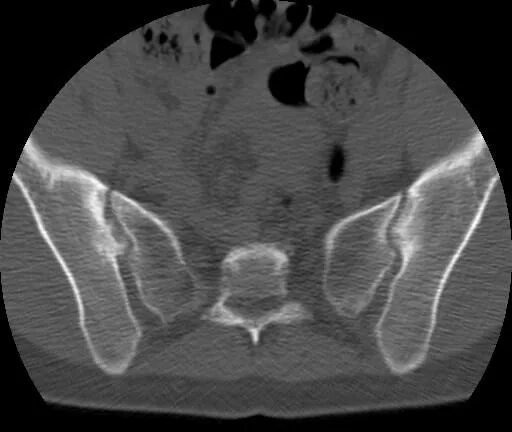

Сакроилеит на кт